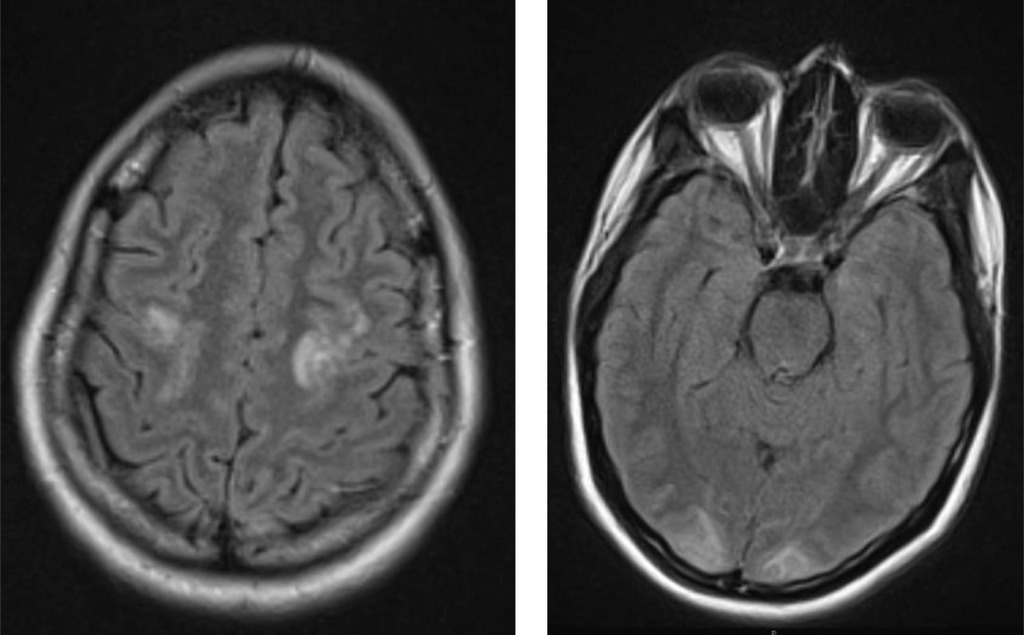

- магнітно-резонансну томографію головного мозку, яка виявила симетричні гіперінтенсивні ділянки в потиличних, тім’яних та лобових частках, характерні для синдрому задньої оборотної енцефалопатії;

Після контролю артеріального тиску повторна магнітно-резонансна томографія показала зменшення вазогенного набряку.